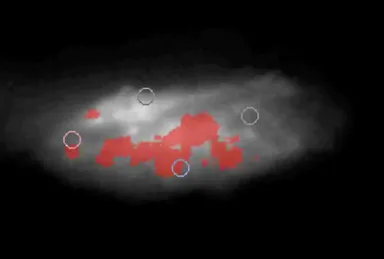

記憶や判断など高度な脳や神経の情報処理活動は、神経細胞の間の神経伝達物質の移動によってなされていることは古くから知られていましたが、生きた脳の中で伝達物質の増減を直接観察する方法はまだ確立されていませんでした。吉見教授は、分子インプリント法で、ターゲットとするセロトニンの分子構造を内部に刷り込んだナノ粒子を合成しました。このナノ粒子は、セロトニンとの特異的な相互作用で、図1のように膨潤し、蛍光強度を増加させる性質があることを確認しました。さらにこのナノ粒子を分散した液にアメフラシ(海に棲むナメクジの仲間)の脳を浸してナノ粒子を吸着させ、蛍光顕微鏡で観察しました。その結果、セロトニンを分泌している箇所で、蛍光強度が激しく増強される様子が確認できました。またセロトニンを分解する酵素を阻害する抗うつ剤を、ナノ粒子で染色した脳に与えると、この蛍光強度の増強はさらに顕著なものとなりました(図2)。

図2:ナノ粒子を吸着させたアメフラシの脳の蛍光画像。セロトニンが分泌されている部分を赤色で示している